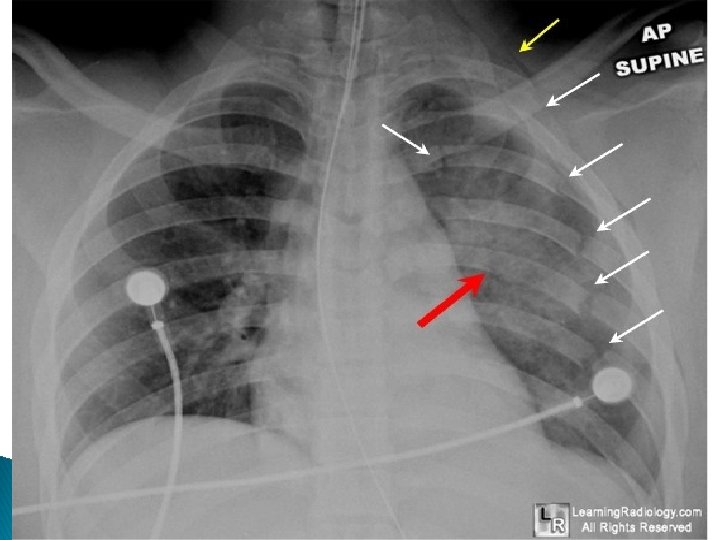

Complications ◦ Pulmonary contusion (almost always) �Airspace disease representing hemorrhage into the alveoli usually subjacent to the point of impact ◦ Pulmonary laceration �Lacerations in the lung may be blood-containing, air-containing, or both �Frequently masked by the surrounding pulmonary contusion ◦ Pneumothorax (very common) �Since the severity of the injury means a supine radiograph will be performed, pneumothoraces may only be seen on chest CT ◦ Hemothorax (common) ◦ Pneumomediastinum ◦ Subcutaneous emphysema ◦ Mediastinal hemorrhage ◦ Aortic injuries